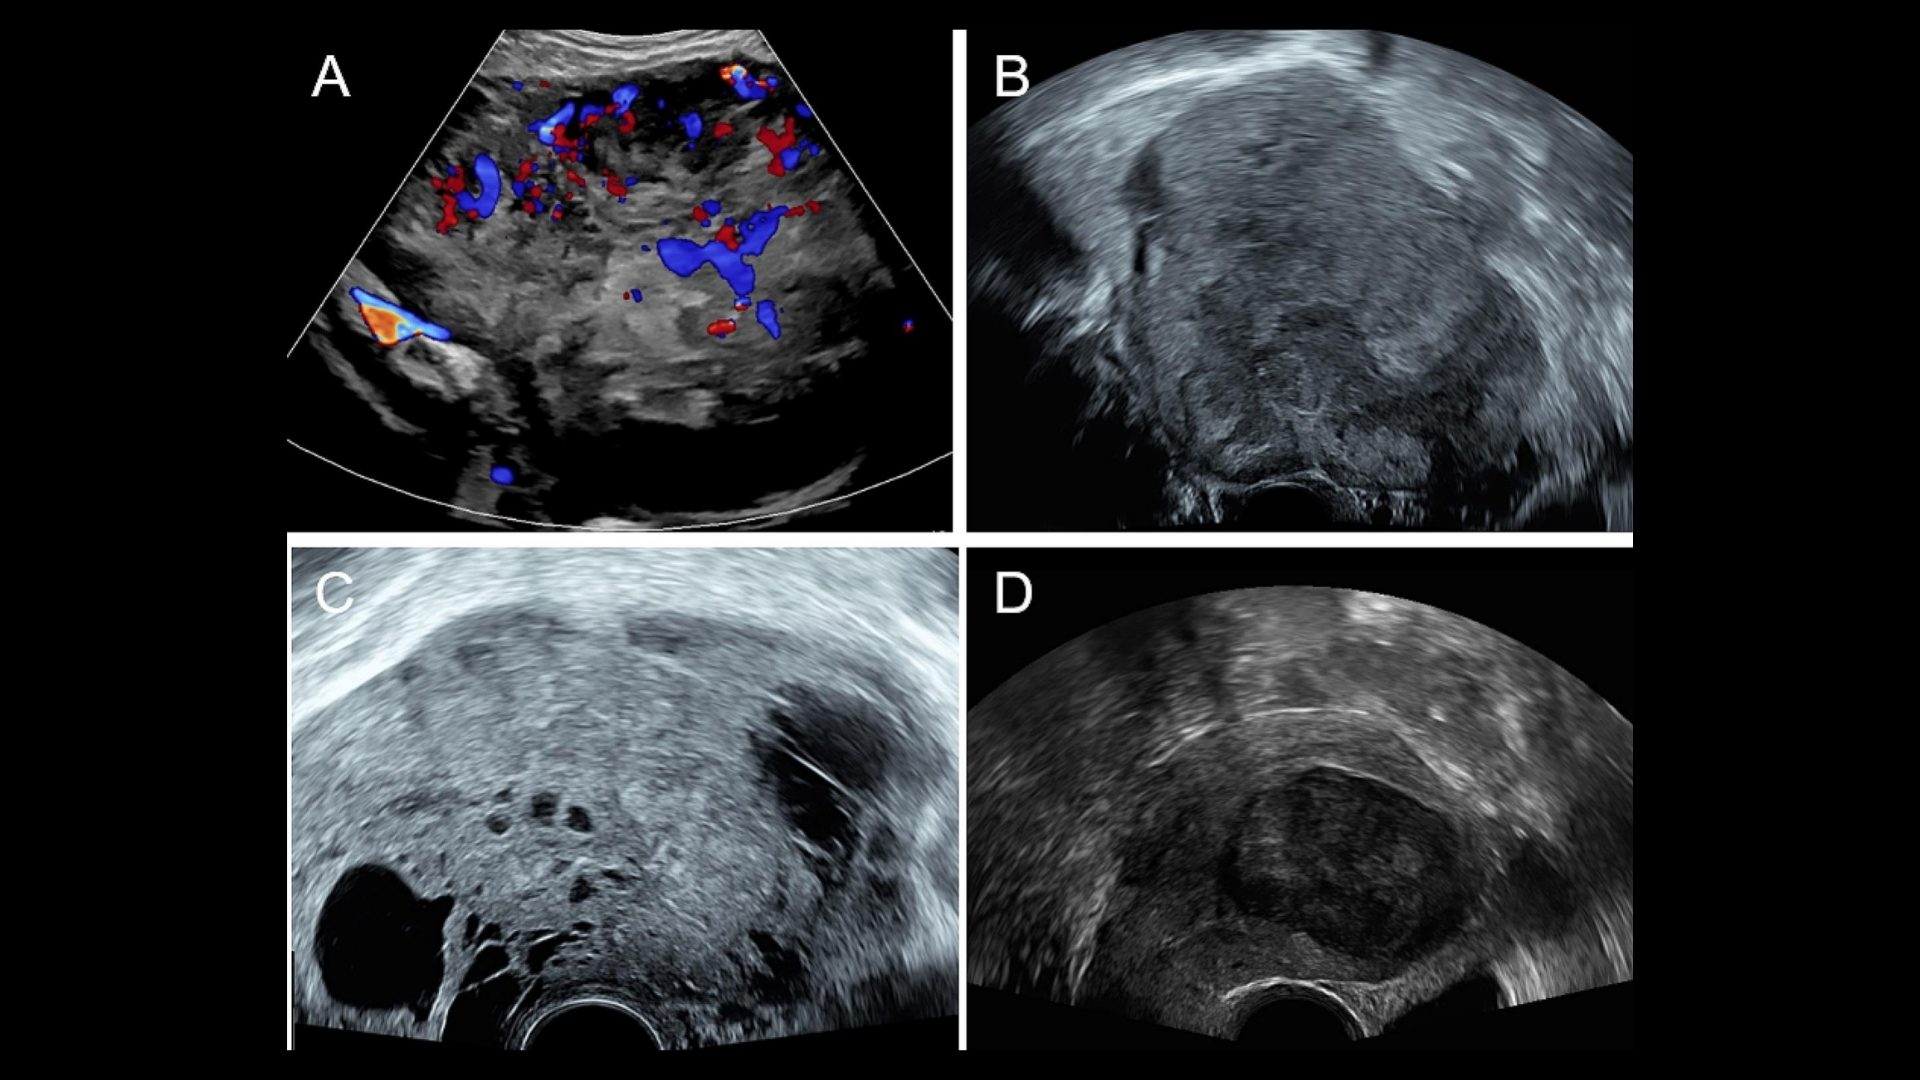

由於這些症狀都是非特異性的,因此準確的診斷需要專家的檢查,通常會使用超音波和先進的影像技術 (MRI 或 CT 掃描)。

• 進階診斷:最先進的影像(例如 PET-CT、Siemens MRI)和分子剖析,以找出腫瘤的代謝漏洞。